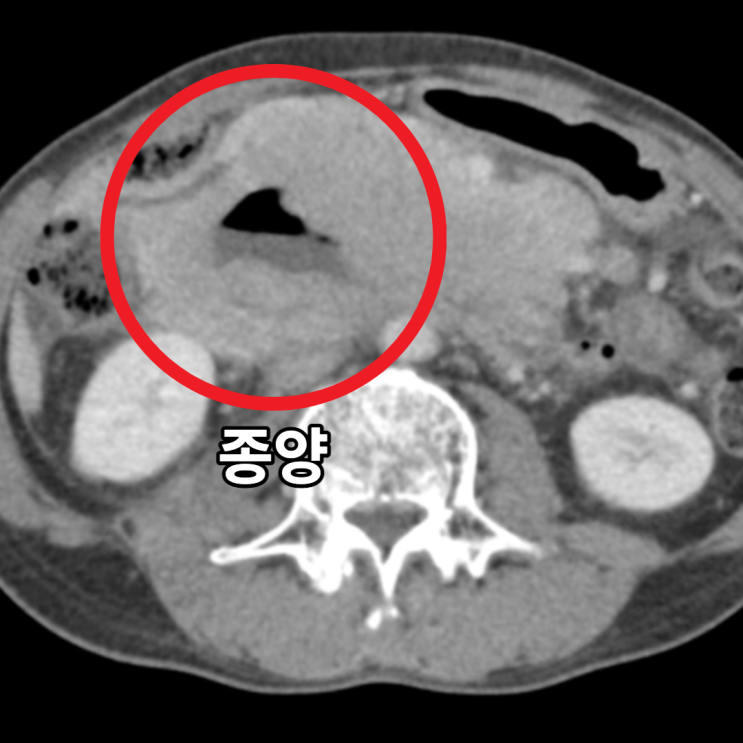

혈액검사에서 큰 이상소견 보이지 않아, 추가로 CT 당일 시행하였습니다. 시행한 복부 CT상에서 불편감을 호소하시는 부위에 약 16cm 크기의 큰 종양이 확인되었으며, 주변 임파선 크기 증가 및 복수가 확인되어, 림프증식성 질환이나 육종등의 종양이 주변 임파선 및 복막으로 전이되었을 가능성이 확인되었습니다.

• 복부CT 횡단면: 약 16cm 크기 종양 확인(빨간 동그라미) 복부CT 횡단면: 약 16cm 크기 종양 확인(빨간 동그라미)